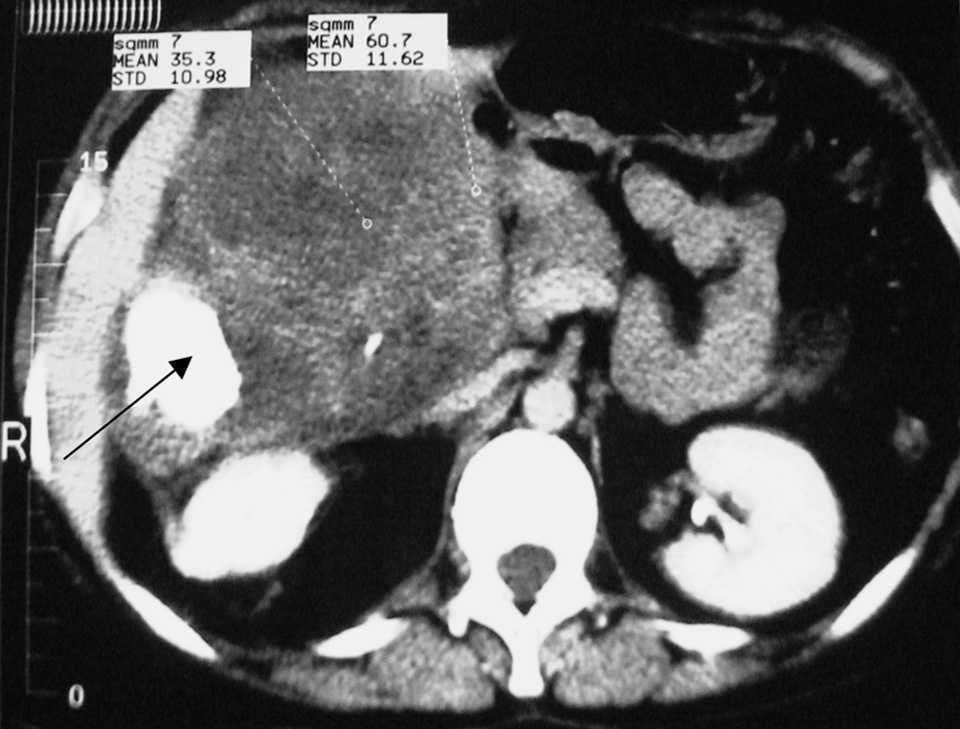

En la exploración física destacaba una masa abdominal palpable en hipocondrio y flanco derecho no dolorosa, firme, no móvil. La analítica general fue normal. Ante el diagnóstico clínico de tumor intraabdominal, se solicitó tomografía computarizada (TC), que evidenciaba tumor retroperitoneal derecho, adherido a riñón con imagen de densidad ósea en su interior (fig. 1).

Fig. 1. Tomografía computarizada abdominal en la que se aprecia una masa retroperitoneal derecha con imagen de densidad ósea.